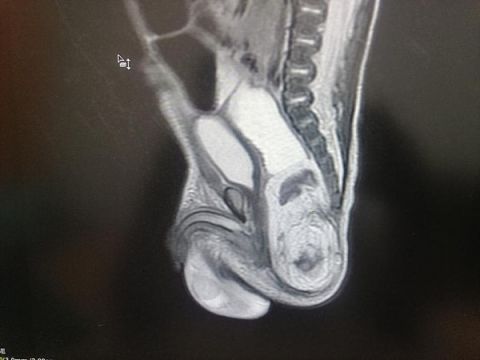

Нейрохирурги детской областной больницы провели крошке операцию, в результате которой удалось полностью удалить врожденную опухоль или тератому.

Такие тератомы бывают злокачественными и дают метастазы. В этом случает требуется специальное онкологическое лечение. Именно поэтому крошке как можно раньше была проведена операция с применением увеличительной техники.

Этому новорождённому повезло - врачи успели удалить образование еще до того, как оно повредило бы окружающие органы. Как отмечают специалисты, у маленького пациента хороший прогноз для развития и дальнейшей жизни.Фото: medkirov.ru